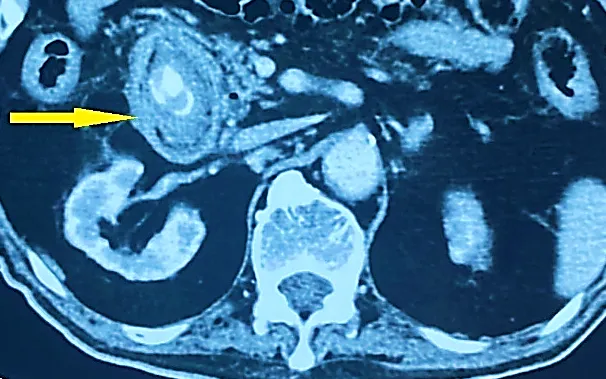

Thực tế tại Bệnh viện Nội tiết Trung ương đã ghi nhận nhiều trường hợp nhập viện khi bệnh đã biến chứng do chủ quan. Điển hình là một người bệnh nam 58 tuổi, có tiền sử đái tháo đường nhiều năm, chỉ xuất hiện đau âm ỉ vùng bụng phải và khó tiêu kéo dài. Tuy nhiên, khi đến thăm khám, các bác sĩ phát hiện người bệnh đã bị viêm túi mật cấp do sỏi và phải phẫu thuật nội soi sớm.

Một trường hợp khác là người bệnh nữ 65 tuổi nhập viện trong tình trạng sốt và vàng da nhẹ nhưng không đau bụng dữ dội. Qua thăm khám và siêu âm, các bác sĩ chẩn đoán tắc mật, nhiễm trùng đường mật do sỏi và phải can thiệp kịp thời để tránh biến chứng nguy hiểm.